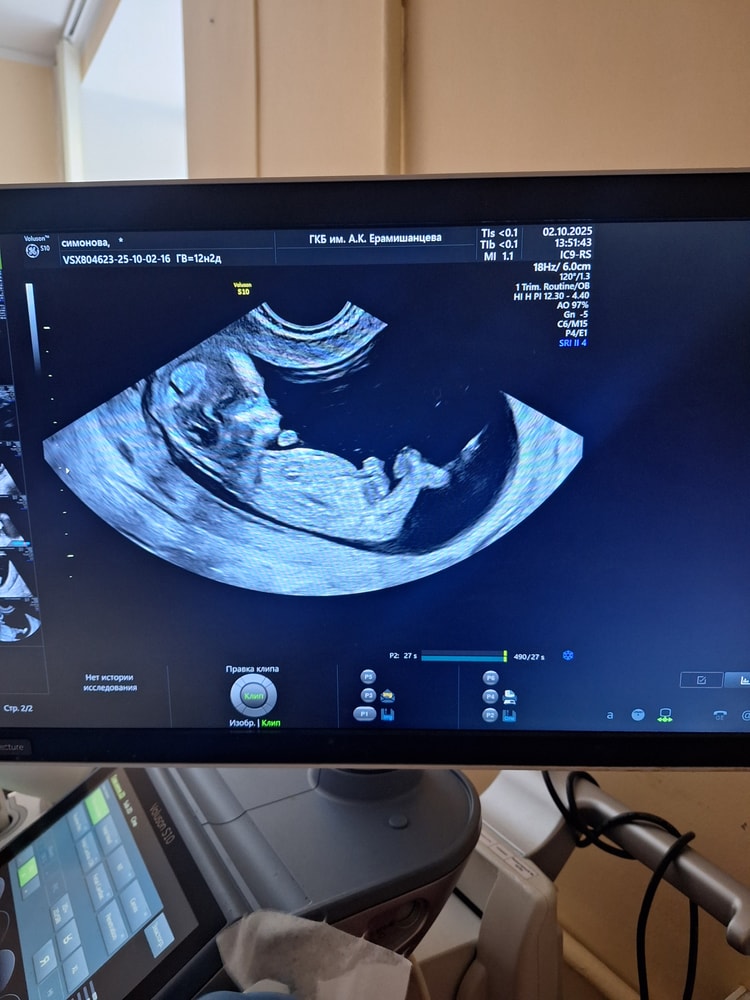

Сегодня по месячным срок 12 недель, гестационный возраст врач узи насчитал 12 недель 2 дня (вообще не поняла, что это за расчет такой и как он больше срока по месячным получился). Сколько по КТР и какая дата ПДР не сказали.

После того как врач все посмотрела и записала все показатели (2 раза через живот и 2 раза трансвагинально), она развернула экран ко мне и дала понаслаждаться моментом)))

6.5 см человека, 1.6 ТВП и 167 уд/мин ЧСС. Вроде все отлично, после НИПТа другого и не ожидала)))

Малышок упирался ножками, пытался вытянуться, махал ручками. Нос показался большим (в папу)))), ноги длинные - мамины))). Ракурс для фото дали не очень удачный, к сожалению, и жаль, что не дали сделать видео и что второго экрана нет.